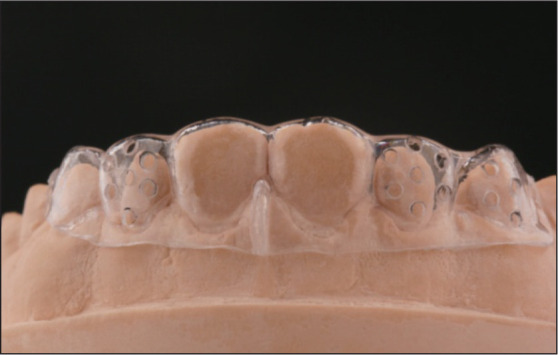

2.2. 以诊断蜡型(wax-up)基础制作的导板或诊断饰面(mock-up)引导的牙体预备

经虚拟或实体设计的诊断蜡型,常用于医患沟通目标修复体外形排列等,并指导最终修复体的制作,又称作蜡型预告。进一步可以使用硅橡胶等材料在口外翻制蜡型形态,以形成导板或在口内使用临时美学修复材料制作诊断饰面用于指导牙体预备,是美学区牙体预备较为经典的方法。1)以诊断蜡型为基础制作的导板引导预备方式,因硅橡胶导板可预先进行切龈向、唇舌向及近远中向方的切割,更易观测目标牙体各轴向的预备形态与预备量变化,因此易用于体内或混合空间如全冠修复的预备。2)以诊断蜡型基础制作的诊断饰面引导的牙体预备,是指在口内参考诊断饰面的表面进行牙体预备(即APT技术)。由于诊断饰面引导预备常使用口内预告方式,故易用于体外空间如贴面修复、过小牙修复等的预备。

除了用硅橡胶进行导板制作外,自凝塑料或透明膜片等材料也可用于诊断饰面导板的制作,早在1984年就有医生使用并配合牙周探针检查预备量[20]。研究[21]显示,这类方法能有效保留釉质,提高粘接效果。这类引导方式使用最终修复体形态作为参考,不再只依赖术者的个体经验,相比经验类比引导方式更加准确(图3)。

图 3. 硅橡胶指示导板引导的牙体预备.

Fig 3 Tooth preparation guided by silicone index

左上:使用硅橡胶指示导板引导下颌前牙切端预备;右上:使用硅橡胶指示导板引导下颌前牙唇侧预备;左下:使用硅橡胶指示导板引导上颌前牙切端预备;右下:使用硅橡胶指示导板引导上颌前牙唇侧预备。

但这类方式也存在一定局限,主流的硅橡胶指示导板(silicon index)其预备量的控制仅为硅橡胶导板切割面,无法覆盖全部预备面,整体上看仍不精确;并且诊断饰面引导中使用的牙周探针测量的刻度为1 mm,小于1 mm数值依然是估算,与0.1~0.3 mm的百微米级牙体预备精度不通洽;另外面对过度扭转或倾斜的基牙时,诊断饰面制作困难或需要预先磨除多余部分才能进行诊断饰面的制作,故此类方法适合于难度较小的改形病例或二次修复。这类方法操作简便,效果相对可靠,适用于简单美学修复病例。